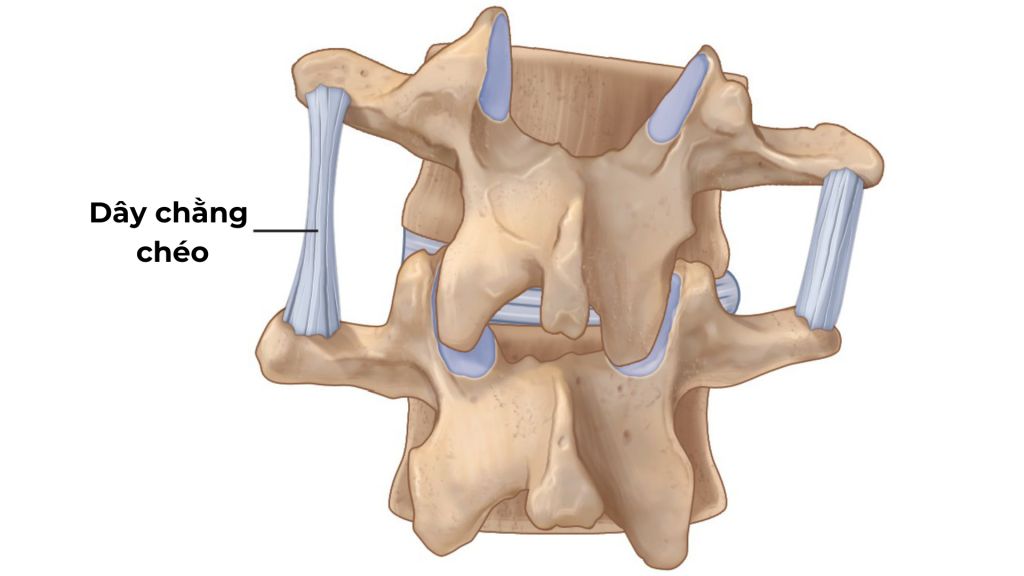

3. Giãn dây chằng lưng

Giãn dây chằng lưng là tình trạng tổn thương các dây chằng ở vùng thắt lưng, thường gặp ở người trẻ tuổi do vận động sai tư thế, mang vác vật nặng đột ngột hoặc tập luyện thể thao quá sức. Bệnh lý này cũng có thể xảy ra do yếu tố di truyền hoặc các chấn thương, va đập mạnh vào vùng lưng.

Các dấu hiệu nhận biết bao gồm đau nhức dữ dội ở vùng thắt lưng, lan xuống mông, hông hoặc chân, căng cứng cơ bắp, hạn chế vận động, mệt mỏi, khó chịu, ảnh hưởng đến sinh hoạt và chất lượng cuộc sống.

Đây là bệnh lý khá phổ biến, có thể dẫn đến đau nhức kéo dài, tăng nguy cơ thoái hóa cột sống, tổn thương dây thần kinh gây tê bì, châm chích, yếu liệt ở chân, từ đó làm giảm khả năng vận động, khó khăn trong việc đi lại, đứng lên, ngồi xuống.

Giãn dây chằng lưng có thể được phòng ngừa bằng việc đảm bảo tư thế đúng, tập thể dục thường xuyên, khởi động kỹ trước khi tập luyện và duy trì cân nặng hợp lý. Bệnh lý này tuy không quá nguy hiểm nhưng cũng cần được chẩn đoán và điều trị kịp thời, tránh biến chứng nguy hiểm. Vật lý trị liệu bằng các bài tập phục hồi giãn dây chằng lưng là một phương pháp phổ biến trong điều trị và đem lại hiệu quả cao.